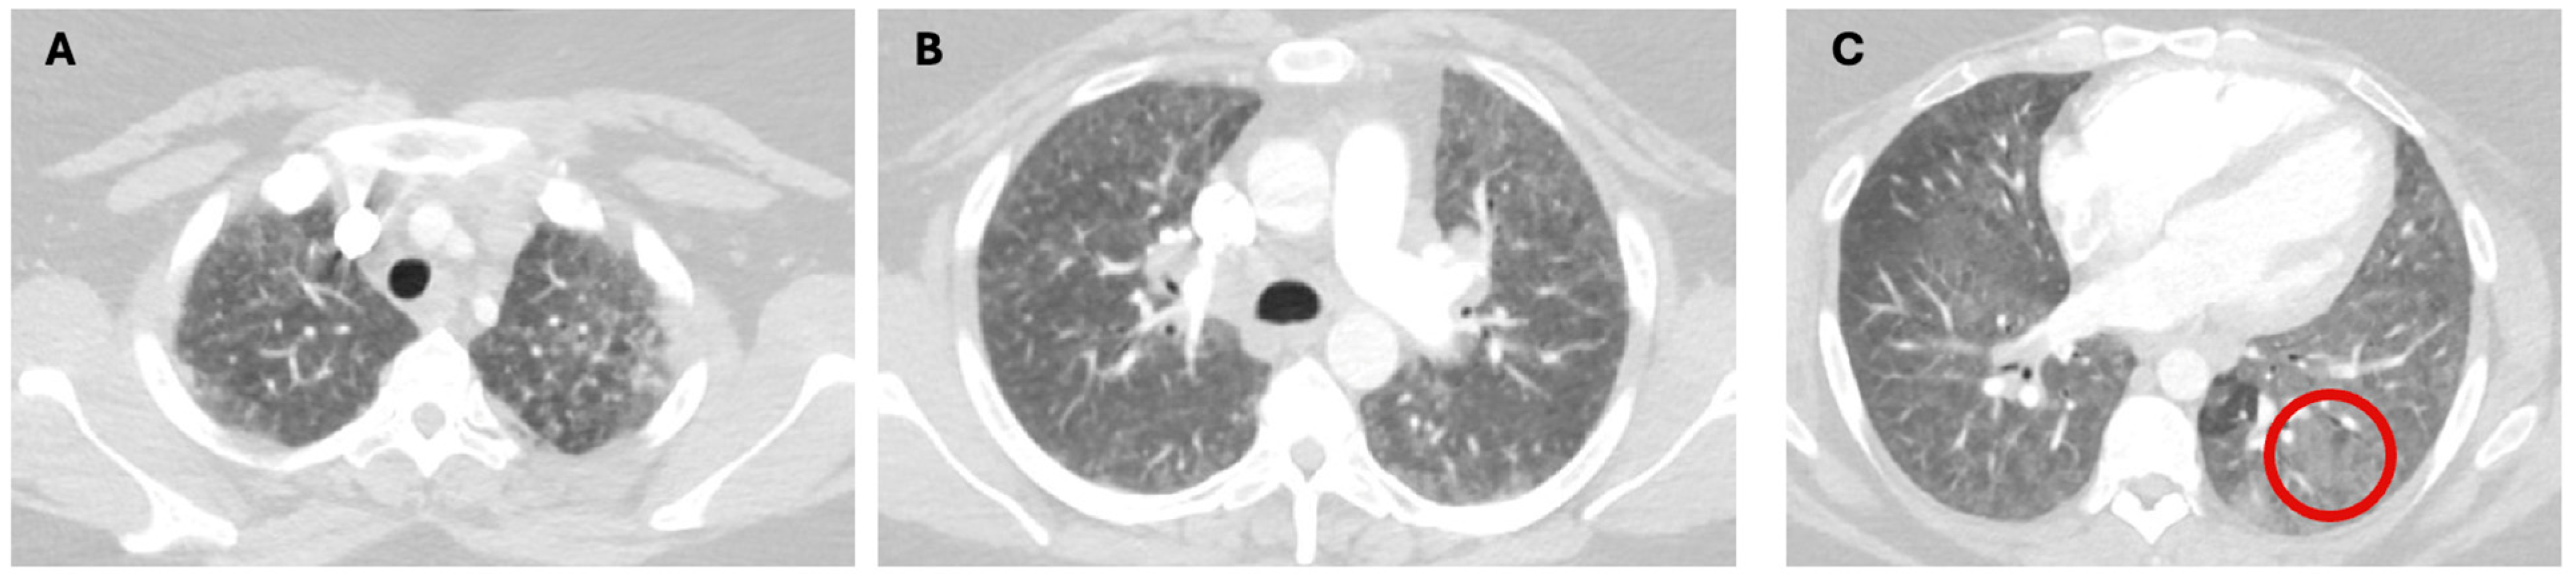

1.1. The Diagnosis and Evaluation of Patients with ILD in the ICU

- Charokopos, A.; Moua, T.; Ryu, J.H.; Smischney, N.J. Acute exacerbation of interstitial lung disease in the intensive care unit. World J. Crit. Care Med. 2022, 11, 22–32. [Google Scholar] [CrossRef]

- Collard, H.R.; Ryerson, C.J.; Corte, T.J.; Jenkins, G.; Kondoh, Y.; Lederer, D.J.; Lee, J.S.; Maher, T.M.; Wells, A.U.; Antoniou, K.M.; et al. Acute Exacerbation of Idiopathic Pulmonary Fibrosis. An International Working Group Report. Am. J. Respir. Crit. Care Med. 2016, 194, 265–275. [Google Scholar] [CrossRef]

- Suzuki, A.; Kondoh, Y.; Brown, K.K.; Johkoh, T.; Kataoka, K.; Fukuoka, J.; Kimura, T.; Matsuda, T.; Yokoyama, T.; Fukihara, J.; et al. Acute exacerbations of fibrotic interstitial lung diseases. Respirology 2020, 25, 525–534. [Google Scholar] [CrossRef]

- Alhamad, E.H.; Cal, J.G.; Alrajhi, N.N.; AlBoukai, A.A. Acute exacerbation in interstitial lung disease. Ann. Thorac. Med. 2021, 16, 178–187. [Google Scholar] [CrossRef]